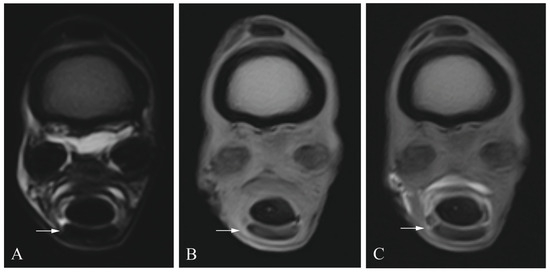

2.3. Diagnostic Imaging

2.4. Image Analysis